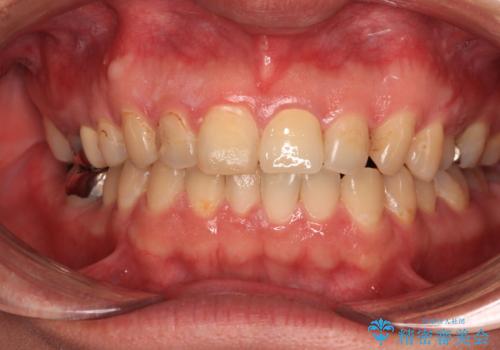

つぎはぎだらけの前歯をオールセラミッククラウンで自然な前歯に

汚れがつきやすい状態のため、今後も継続してクリーニングを行っていく必要があります。